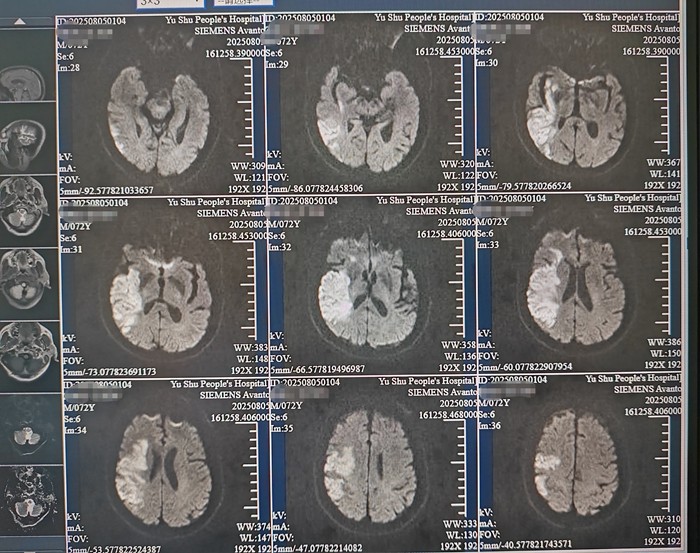

8月2日上午,来自昆明的游客周先生突然出现头痛头晕、左侧肢体无力、言语含糊的症状,中午12时许,他被120送到玉树州人民医院。“我们第一时间启动卒中绿色通道,对患者的情况进行全面评估。”北京第六批第一期援青医疗团成员,玉树州人民医院卒中中心(神经内科)和介入科主任佟旭说,评估发现周先生言语含糊,左侧肢体肌力显著下降(上肢2级、下肢3级),头颅CT确诊为“右侧大脑半球急性脑梗死”,NIHSS评分高达12分(分数越高,说明神经受损越严重)。

溶栓治疗30分钟后,患者左侧肢体肌力明显改善,2小时后语言功能开始恢复。正当大家松了一口气时,次日清晨,周先生的病情出现波动,意识水平下降呈嗜睡状态,出现向右侧凝视、不完全运动性失语和左侧肢体瘫痪(肌力1级)。“复查CT显示,患者并未发生脑出血,MRI证实,他的右侧大脑中动脉闭塞,梗死面积扩大。”佟旭说,血栓进展迅速,在溶栓后24小时内启动抗血小板治疗又有可能引发出血,医疗团队被“挤”到“死胡同”。医疗团队判断导致再次脑梗的原因是大脑中动脉存在不稳定斑块继发血栓反复或进展,经过反复权衡、判断,决定立即进行负荷剂量双抗治疗,同时联合强化降脂稳定斑块的治疗方案,为了减轻大面积脑梗死后脑水肿可能导致的严重后遗症,佟旭根据丰富的临床经验,精确计算周先生脑水肿的发生、加速、高峰和消退期,并打破传统,使用更加有效果的药物和给药方式。